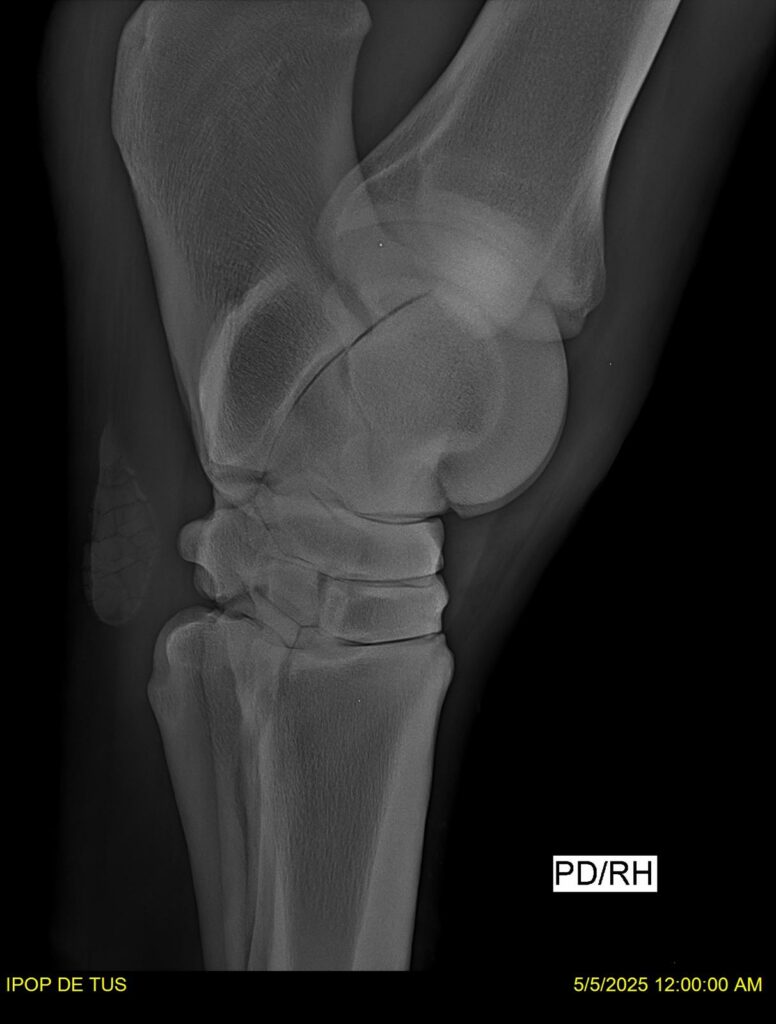

IPOP DE TUS, selle français, hongre, prendra 8 ans en 2026. LIFESTYLE x EROTICBLUS MONTOIS. Sans faute sur 125 et 130. Gentil cheval, respectueux avec des moyens et de la force. Transport OK, maréchalerie OK (pieds nus), santé RAS, Bilan clichés radios + clinique OK.

RADIOS ET CLINIQUE